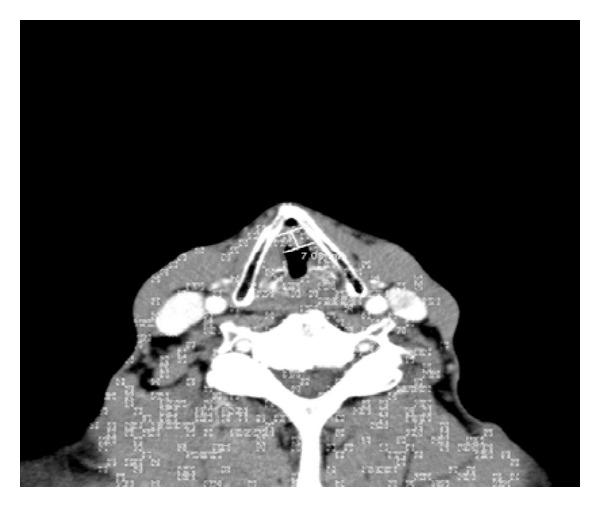

Spindle cell carcinoma (SpCC) or sarcomatoid carcinoma is a highly malignant variant of squamous cell carcinoma which comprises 2% to 3% of all laryngeal cancers. It is considered to be a biphasic tumor that is composed of a squamous cell carcinoma (in situ or invasive) and spindle cell carcinoma with sarcomatous appearance. Most spindle cell tumors are polypoid and pedunculated; they are often detected at an early stage, removed by polypectomy during diagnosis, and tend to have a very good prognosis. We present a case of spindle cell carcinoma in a 67-year-old Caucasian male who presented with progressive hoarseness of his voice, dysphagia, odynophagia and a 20-pound weight loss. The patient underwent direct laryngoscopy with excision of the malignant mass and received radiation therapy. His symptoms gradually improved, and he regained good control of his voice.

梭形细胞癌(SpCC)或肉瘤样癌是鳞状细胞癌的一种高度恶性变体,占所有喉癌的2%至3%。它被认为是一种双相肿瘤,由鳞状细胞癌(原位或浸润性)和具有肉瘤样外观的梭形细胞癌组成。大多数梭形细胞瘤呈息肉样且有蒂;它们常在早期被发现,在诊断时通过息肉切除术切除,预后往往非常好。我们报告一例67岁白种男性梭形细胞癌病例,该患者表现为进行性声音嘶哑、吞咽困难、吞咽疼痛和体重减轻20磅。患者接受了直接喉镜检查并切除恶性肿块,随后接受了放射治疗。他的症状逐渐改善,声音也恢复了良好的控制。